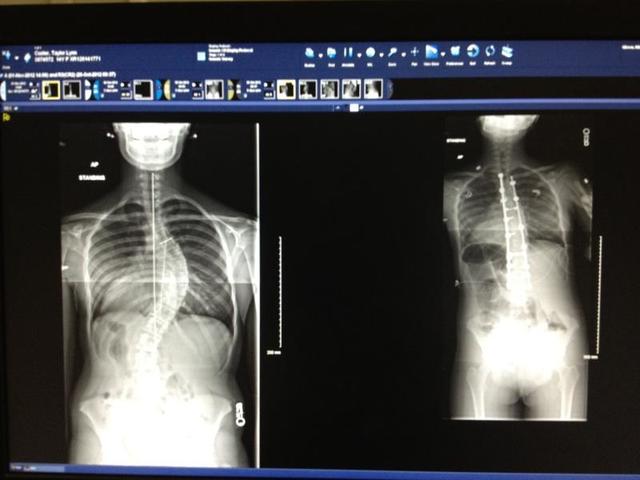

My Back Surgery 2012 - Present Day

I had my first doctor's appointment at Shriner's Children Hospital in Greenville, South Carolina.

Scoliosis Diagnosis and Treatment